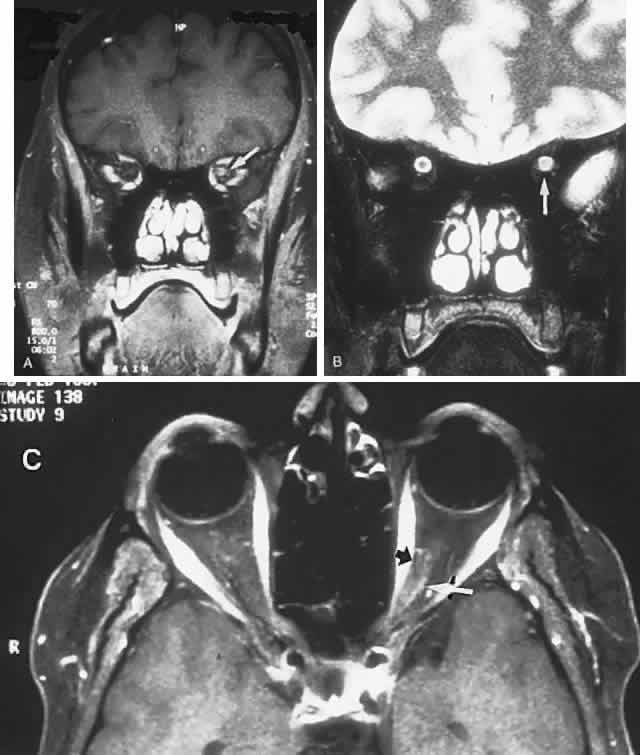

Fig. 1. A 14-year-old boy referred for occult neurologic disease or malingering who had undergone magnetic resonance imaging and psychiatric counseling. Visual acuity was 20/100 in both eyes. Fundi (A and B) show thinned rounded macular reflexes and mild pigment changes at the foveae. Fluorescein angiography (C) disclosed marked macular pigment epithelial disturbance. Diagnosis: juvenile macular degeneration (Stargardt's type).

Fig. 3. Cone-rod dystrophy or so-called “retinitis pigmentosa inversa” in a young man with progressive spinocerebellar degeneration and 20/200 acuity in each eye.

The retinal variety may be admixed in a person who suffers the more conventional attacks of migraine. It is presumed that vasospasm in the retinal circulation determines transient hypoxia, perhaps somewhat similar to the visual cortical event. On rare occasions, the fundus has been examined during typical retinal migraine episodes, and arterial constriction has been described. Wolter and Burchfield106 photographically documented such an episode and demonstrated mild “retinal edema”; vessel narrowing is also evident (Fig. 8). Fortunately, permanent complications of retinal migraine are rare. These may take the form of central retinal artery occlusion or ischemic papillopathy (see Volume 2, Chapter 16); nerve fiber bundle visual field defects may be demonstrated (Fig. 9).

Fig. 8. Retinal migraine. A. During amaurotic episode. Note the dusky appearance of the fundus, increased retinal sheen (possibly edema), and dark narrowed veins (arrows). The disc is also hyperemic. B. Fundus after episode. Compare paired arrows. (Courtesy of Dr. J. Reimer Wolter)